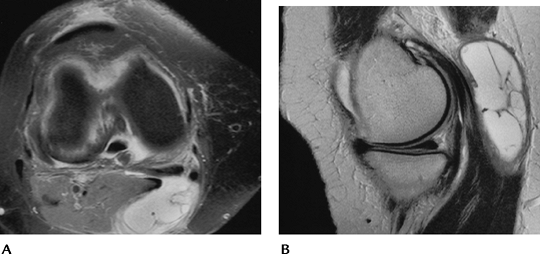

FIGURE 5-53 Sagittal (A) and axial (B)

T2-weighted MR images after patellar dislocation with fluid–fluid levels, retinacular tear, and shaving of the patellar articular cartilage (arrow). |